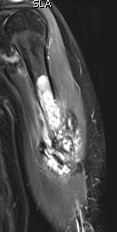

Osteosarcoma of the humerus Osteosarcoma of the fibula

MRI

Evaluate

i) Soft tissue component

ii) Involvement of neurovascular bundle

iii) Marrow extent of tumour

- helpful in determining appropriate resection level

- satellite lesions - metastasis within reactive zone

iv) Identify skip lesions

- metastasis outside reactive zone

- sagittal and coronal images of the entire bone

v) Joint involvement